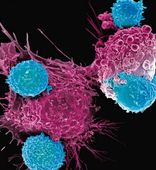

Клеточная терапия

Институт биофизики и клеточной инженерии НАН Беларуси занимается разработкой биомедицинских клеточных продуктов (БМКП) — на данную деятельность учреждение имеет все необходимые документы. БМКП используются при лечении онкологических, неврологических и аутоиммунных заболеваний.

На базе Института действует отделение клеточной терапии (ОКТ): именно здесь занимаются диагностикой и лечением непростых заболеваний с использованием современных методик, в основе которых лежат клеточные технологии. ОКТ предоставляет медицинские услуги в области аллергологии и иммунологии, онкологии и лабораторной диагностики.

- Клеточная терапия сложных заболеваний